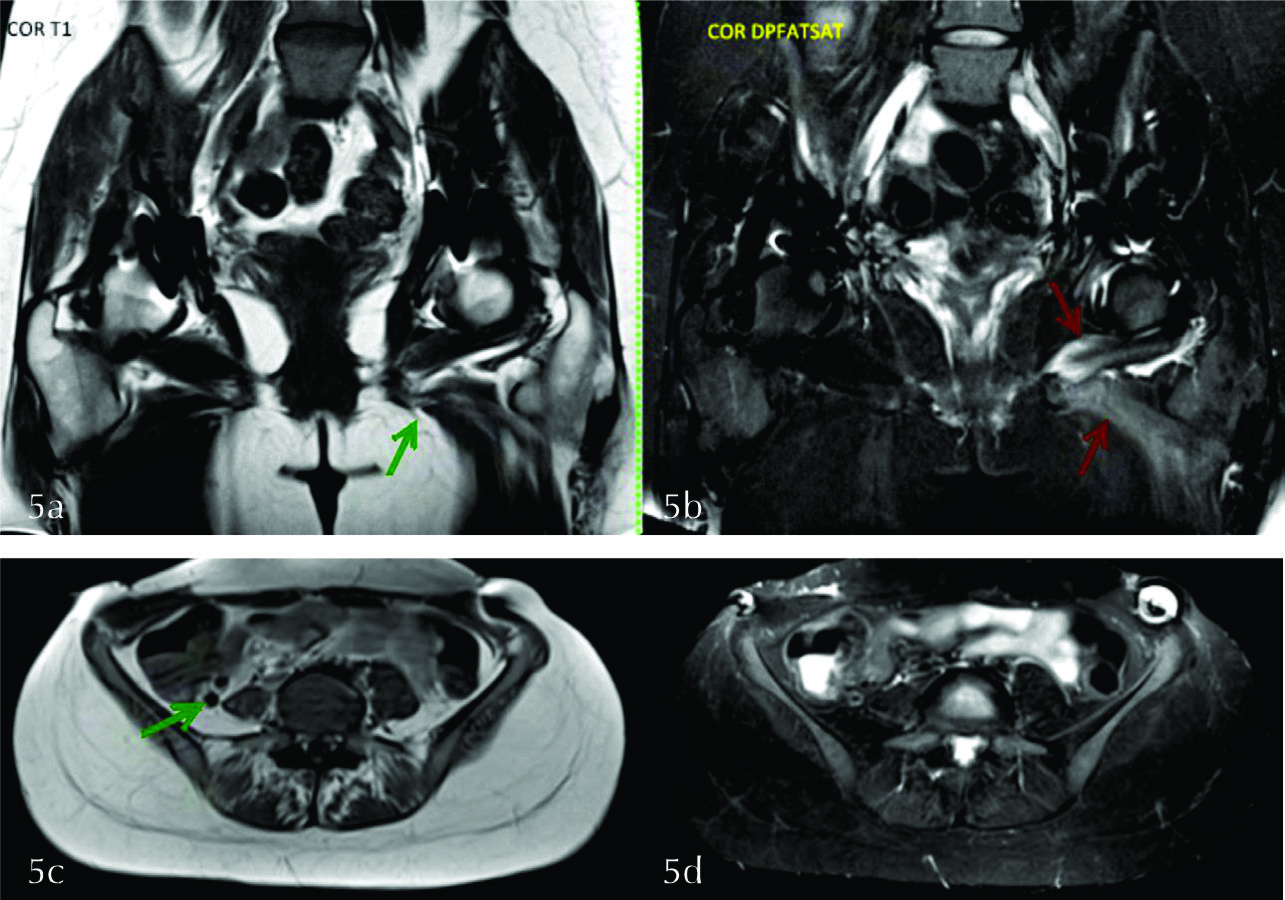

A izquierda se visualiza edema en el músculo obturador externo y aductores, con atrofia de los mismos, compatible con denervación subaguda en territorio del nervio obturador (fig. 5 a y b).

A derecha se observa atrofia del músculo psoas, sin edema, compatible con signos de denervación crónica por secuela de lesión del nervio femoral (fig. 5 c y d).

Dados los hallazgos se planteo lesión post quirúrgica del nervio obturador izquierdo en fase subaguda y del nervio femoral derecho en fase crónica.

Figura 5

a y b) Imágenes coronales donde se evidencian artificios en ambas caderas en relación a los antecedentes quirúrgicos. Se visualiza edema en los músculos obturador externo y aductores a izquierda (flechas rojas en b), con disminución de tamaño de los mismos en secuencia T1 (flecha verde en a). c y d) Se observa atrofia del psoas derecho, sin edema (flecha verde).